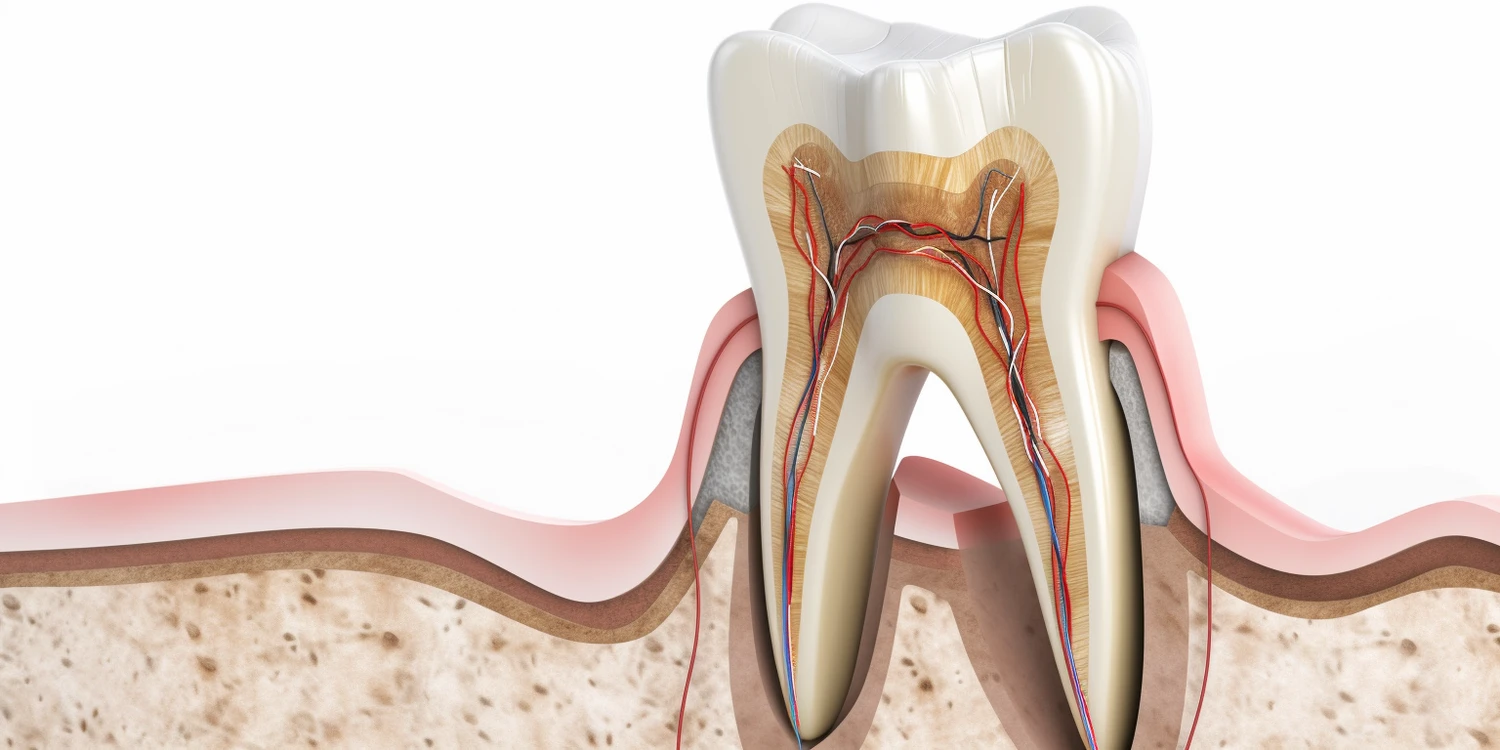

Leczenie kanałowe to procedura stomatologiczna mająca na celu uratowanie zęba przed ekstrakcją poprzez usunięcie chorej miazgi i oczyszczenie kanałów korzeniowych. Wielu pacjentów obawia się bólu związane z tym zabiegiem; jednak dzięki nowoczesnym metodom znieczulenia oraz technikom leczenia ból ten jest zazwyczaj minimalny lub wręcz nieodczuwalny podczas samego zabiegu. Dentysta stosuje miejscowe znieczulenie, które skutecznie eliminuje ból podczas usuwania miazgi oraz czyszczenia kanałów korzeniowych. Po zakończeniu leczenia pacjenci mogą odczuwać pewien dyskomfort związany z procesem gojenia tkanek; jednak zazwyczaj można go złagodzić za pomocą leków przeciwbólowych zaleconych przez dentystę.